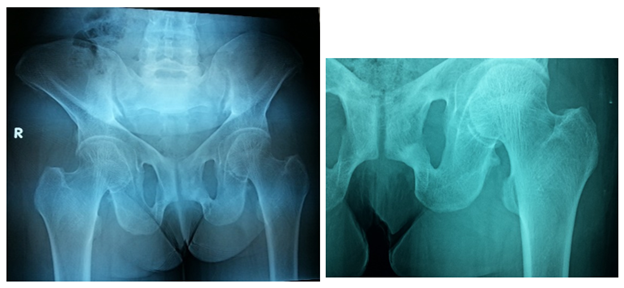

The Pelvis is markedly triradiate, with coarsening of the trabeculation of the femoral head and neck. The femoral heads have lost their normal smooth rounded outline, and are now showing relative flattening, there is a linear translucency in the sub-trochanteric region of the left femur and right inferior pubic ramus suggesting Looser’s zones Figure 4–7. The most impressive features of osteomalacia are the x-ray findings of what is considered to be diagnostic in osteomalacia. Pathologically, they are pseudo fractures except might rarely be present in Paget's disease. It appears as a thin, translucent band. Looser's zones are incomplete stress fractures that heal with callus which is poorly mineralized by calcium. They are frequently seen in the pubic bone, the necks of the femurs, and less frequently humerus and at the edge of the scapulae Figure 8.

Figure 4 Frontal X-ray of the pelvis shows Triradiate pelvis, with coarsening of the trabeculation of the femoral head and neck. The femoral heads have lost their normal smooth rounded outline and are now showing relative flattening. There is bilateral protrusion acetabula and there is a linear translucency in the subtrochanteric region of the left femur suggesting pseudo fracture or Looser’s zone.